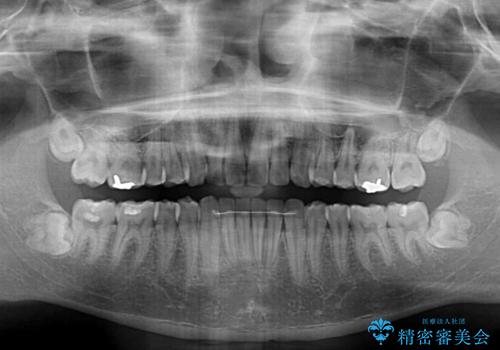

写真より左側臼歯の咬合がタイトではないことが分かりますが、こちらは保定期間に徐々に咬合させていくこととしました。